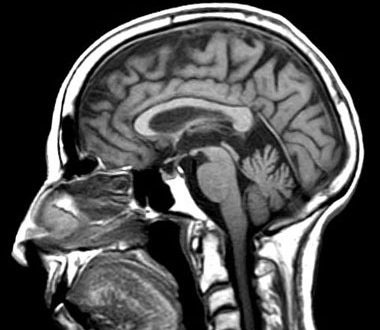

Η εγκεφαλική μελέτη με την τεχνική της λειτουργικής μαγνητικής απεικόνισης (fMRI) αποκάλυψε ένα «ίχνος»», με βάση το οποίο μπορεί να προβλεφθεί αν ένας χρήστης θα θελήσει να μοιρασθεί το άρθρο με άλλους. Το «σήμα» αυτό αντανακλά το πόσο πολύτιμη φαίνεται μια πληροφορία στον αναγνώστη και πόσο πολύτιμη θεωρεί ότι θα είναι επίσης για την κοινωνία.